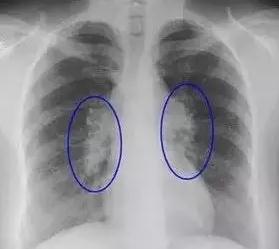

1. 肺部結節:一般年齡大、肺部有基礎疾病的人,做檢查易發現肺部結節。即使發現肺部結節也不必恐慌,因為其中只有極少部分人最后被證實是肺癌。此時必須找專業醫生鑒別判斷:對于小于5毫米的微小結節,僅做隨訪觀察,3個月到半年重新做一次CT檢查。如結節沒有變化、沒有異常增大,一般被認為是沒有風險的,有的甚至會隨著時間變化慢慢消失。1厘米以上的大結節,建議要盡早診治。

肺部結節